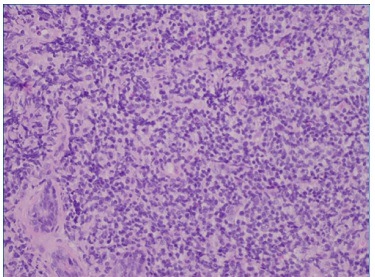

As hipóteses colocadas para diagnóstico diferencial desta lesão apresentadas foram tumores de células salivares (adenoma pleomórfico, carcinoma muco‑epidermoide e adenocarcinoma polimórfico de baixo grau), abcesso de origem dentária/endôntica ou de origem periodontal, e neoplasia linfoproliferativa. Deste modo, procedeu‑se à biópsia incisional que revelou, a nível submucoso, a existência de glândulas mucosas rodeadas por denso infiltrado de células linfoides com vago padrão nodular, assim como espessamento hialino acentuado periductal (Figura 4). Os linfócitos apresentavam tamanho pequeno a intermédio com núcleos hipercromáticos e irregulares, sem lesões linfoepiteliais. A análise imunohistoquímica, revelou expressão de CD20 generalizada com CD10 positivo em áreas nodulares, assim como BCL‑2 e BCL‑6 (Figuras 5, 6 e 7). Estas alterações eram compatíveis com linfoma B folicular, com envolvimento de glândulas salivares minor.

Figura 5 Análise imunohistoquímica, evidenciando positividade para CD10

Figura 6 Análise imunohistoquímica, evidenciando positividade para CD20

Figura 7 Análise imunohistoquímica, evidenciando positividade para BCL‑ 2 e BCL.6